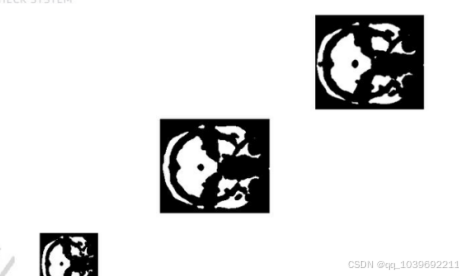

4.1图像分割效果对比

(A1)MRI原始图像 (A2)MRI原始图像 (A3)MRI原始图像 (A4)MRI原始图像

(B1)灰度增强(B2)灰度增强(B3)灰度增强(B4)灰度增强

(C1)去除无意义部分(C2)去除无意义部分(C3)去除无意义部分(C4)去除无意义部分

(D1)本文算法分割 (D2)本文算法分割 (D3)本文算法分割 (D4)本文算法分割

(E1)提取连通域(E2)提取连通域(E3)提取连通域(E4)提取连通域

(F1)填充凹陷部分 (F2)填充凹陷部分 (F3)填充凹陷部分 (F4)填充凹陷部分

4.2关于图像分割的效果说明

鸽脑MRI图像不同于自然图像,大多数的鸽脑MRI图像都具有噪声点多、分辨率低、边界模糊、对比度低以及纹

理、灰度、光照不均匀等特点。[25]基于迭代阈值法处理鸽脑MRI图像,通过原始MRI图像与本论文算法处理后的图

像对比,多组人眼定性分析,基本达到了令人满意的效果。

因此本篇论文基于阈值分割的方法在处理鸽脑MRI图像。目标是分离出鸽脑MRI图像中的脑干部分,去掉脑壳和

其他不相干部分。目的是帮助医生快速准确的识别脑干形状,以便做下一步诊断。本文从医院公开数据库中选用4张

具有代表性的MRI图像,第1张图像展现部分视顶盖区域,第2、3、4张图像有完整的大脑和视顶盖区域。(A1)-

(F1)分别为原始MRI图像、对原始图像进行线性灰度增强、去除小而无意义的组织部分 、通过迭代式阈值法对图像

进行分割、去除外壳和其他组织、填充被腐蚀部分,并用多组人眼对目标区域分割进行评判。